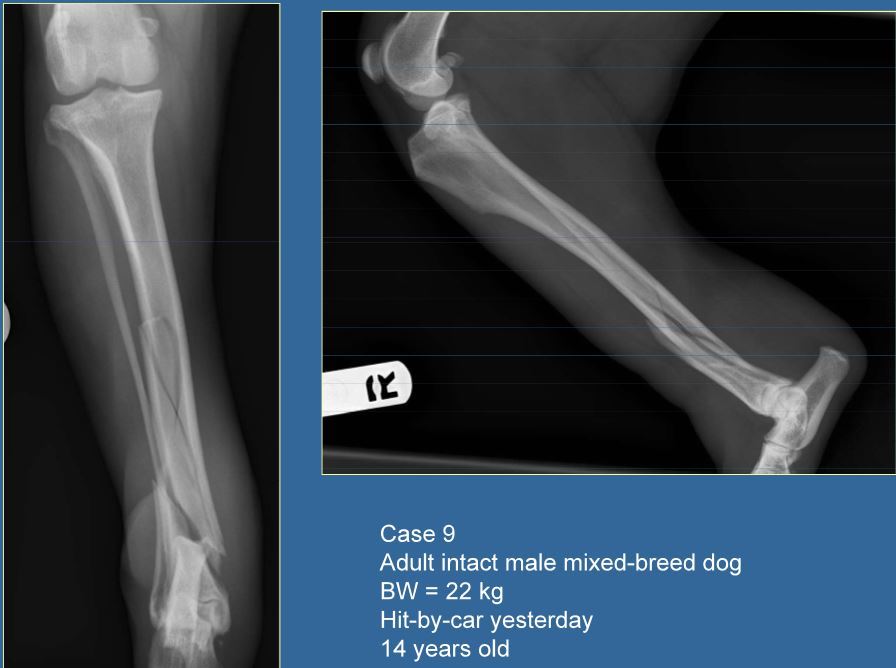

Q

14 year old M mixed breed dog, 22kg

HBC yesterday

Classify and assess fracture, and give repair options

A

Spiral fracture of the distal to mid diaphyseal femur

Fx score= 0 (AGE!)

Repair: Type 2 ESF spanning the articular surface place in a CLOSED fashion